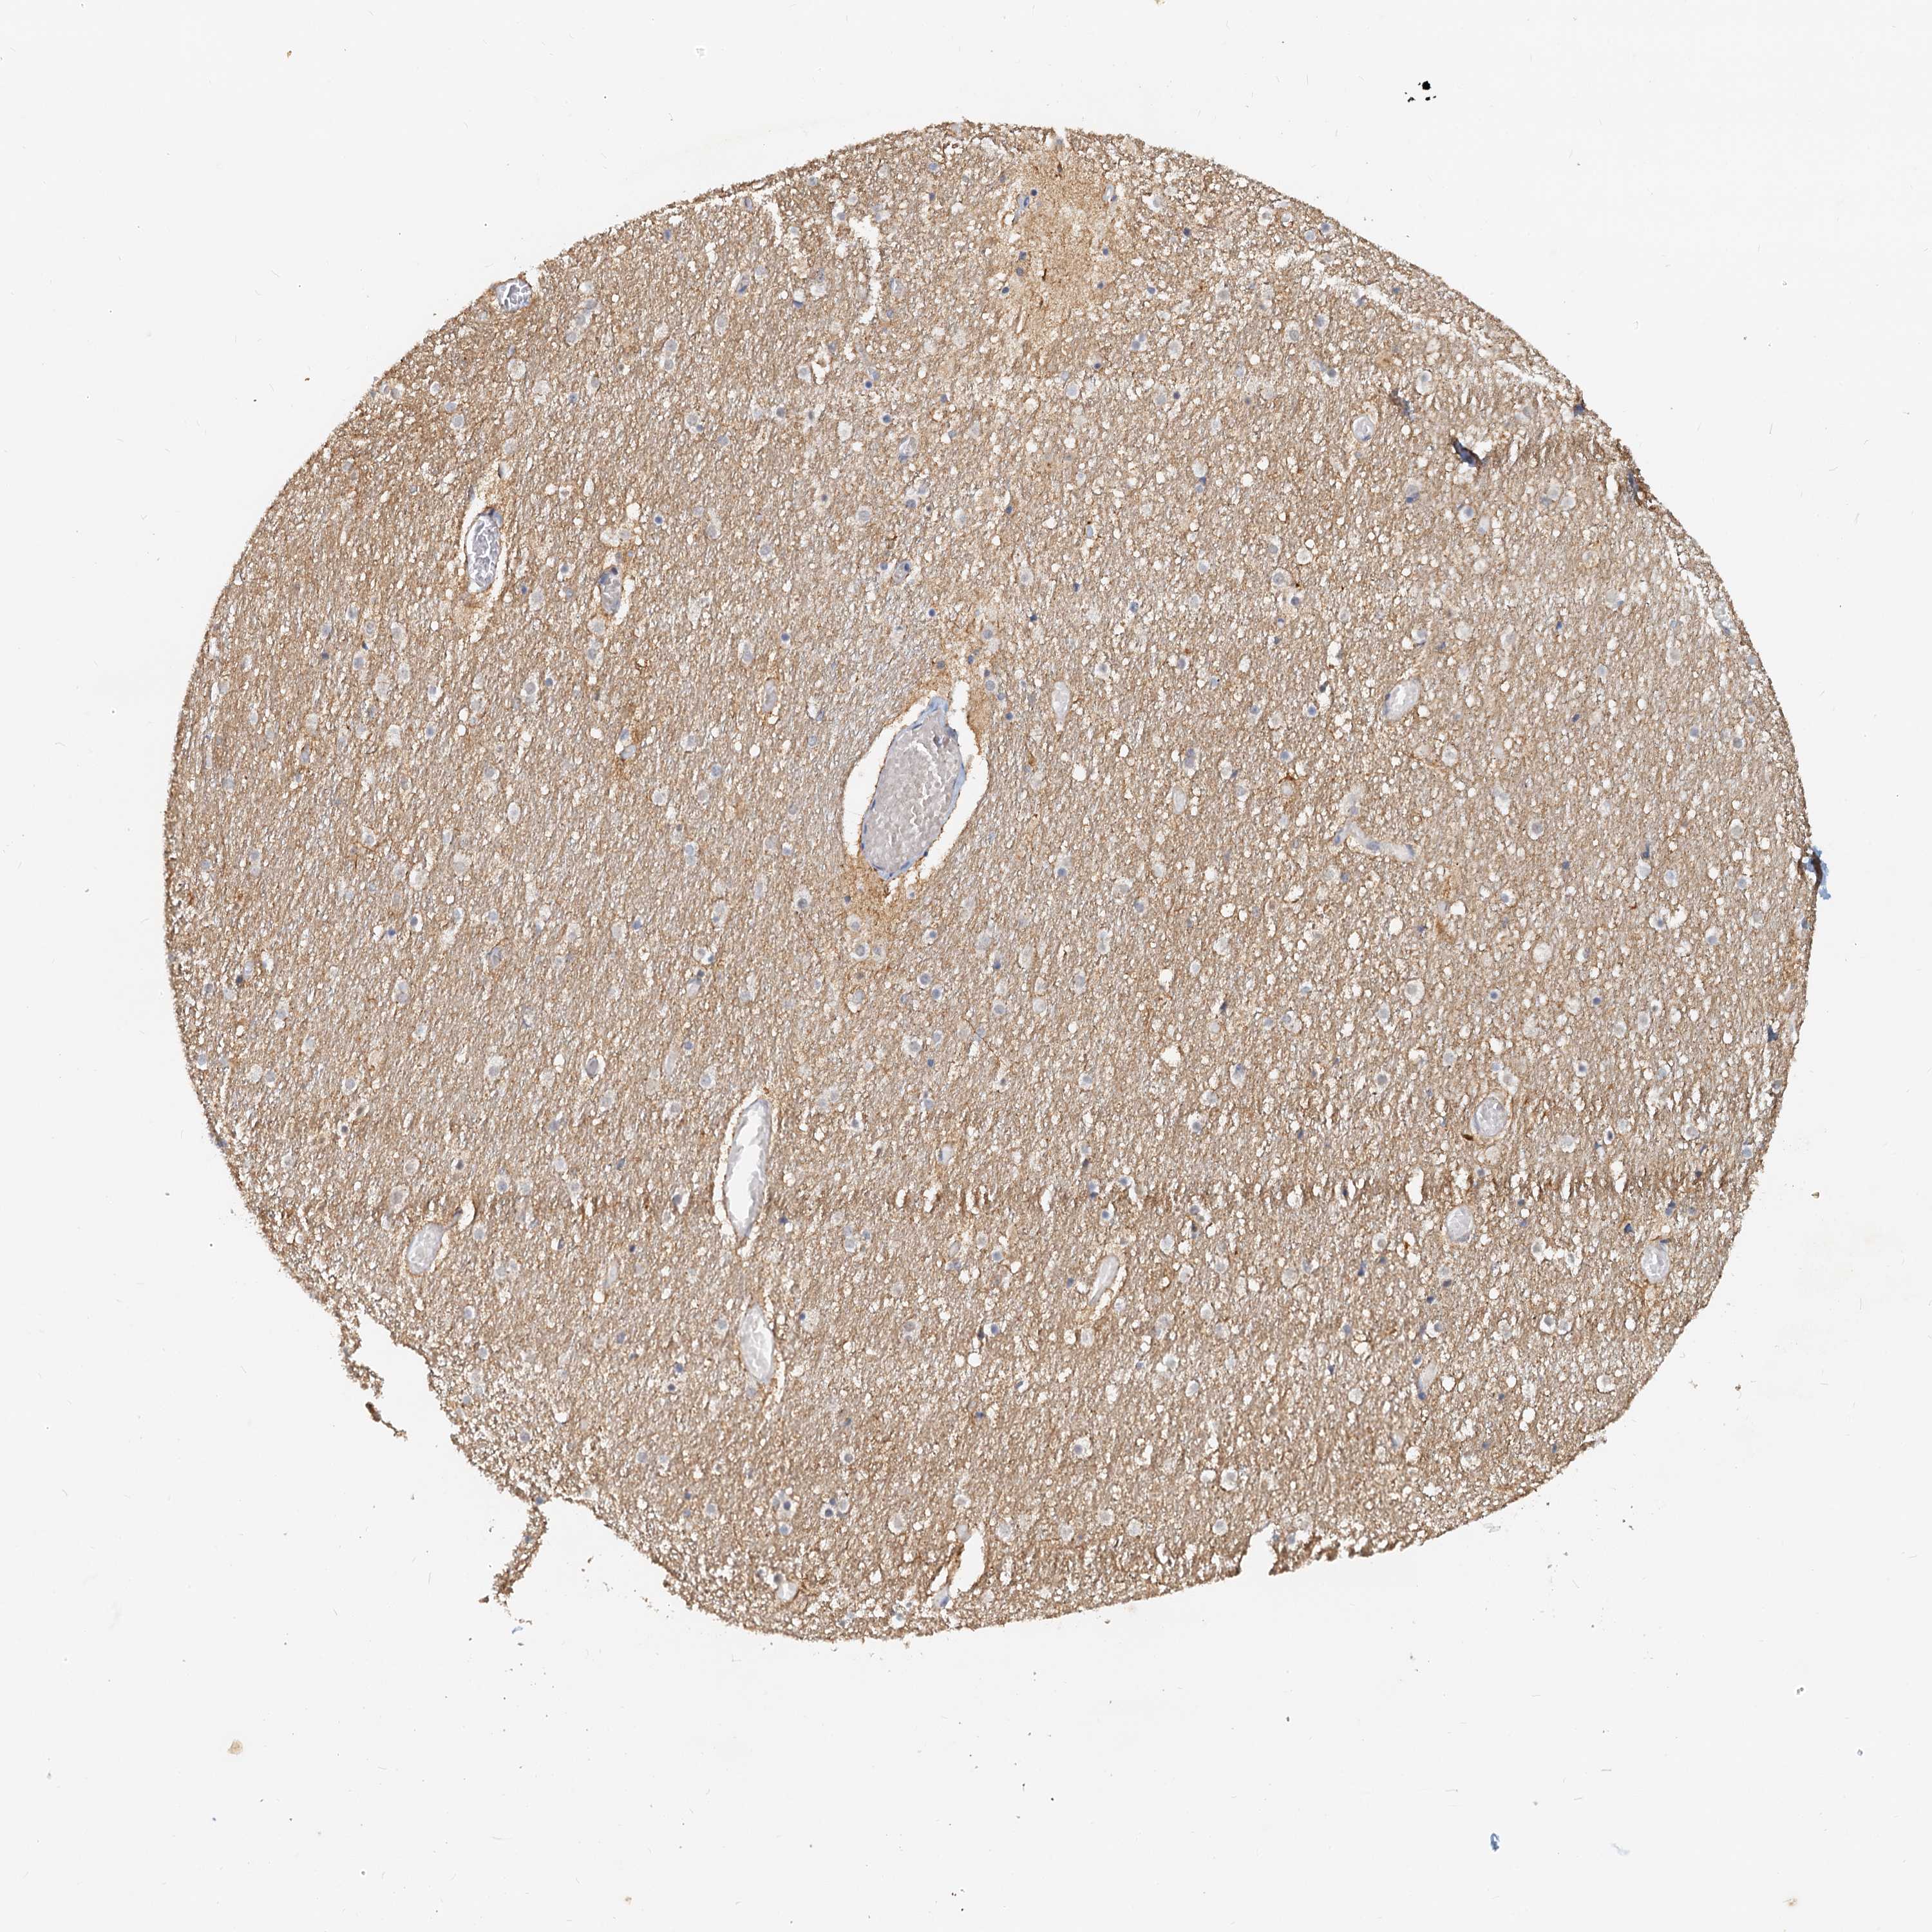

Antibody staining in the annotated cell types in the current human tissue is reported as not detected, low, medium, or high. This score is based on the staining intensity and fraction of stained cells.